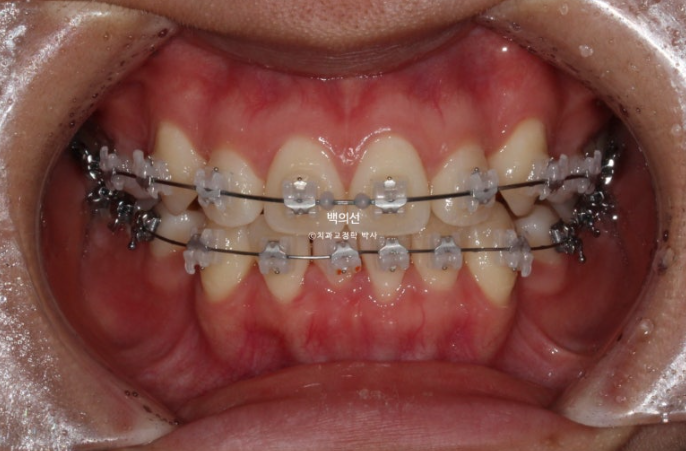

24.01

치료시작 6개월째 모습입니다.

상대적으로 하악 보다 상악이 덧니가 심해 상악을 먼저 붙여서 4개월 정도 덧니배열을 먼저 한 후 하악을 나중에 붙였습니다 브라켓 장치 붙이는 시간을 최소화 해야 환자분이 편합니다.

치료 기간 내내 앞니가 뒤로 들어가는 것을 최소화 하고자 발치공간으로 어금니를 하나씩 앞으로 당겨오는 치료를 했습니다.